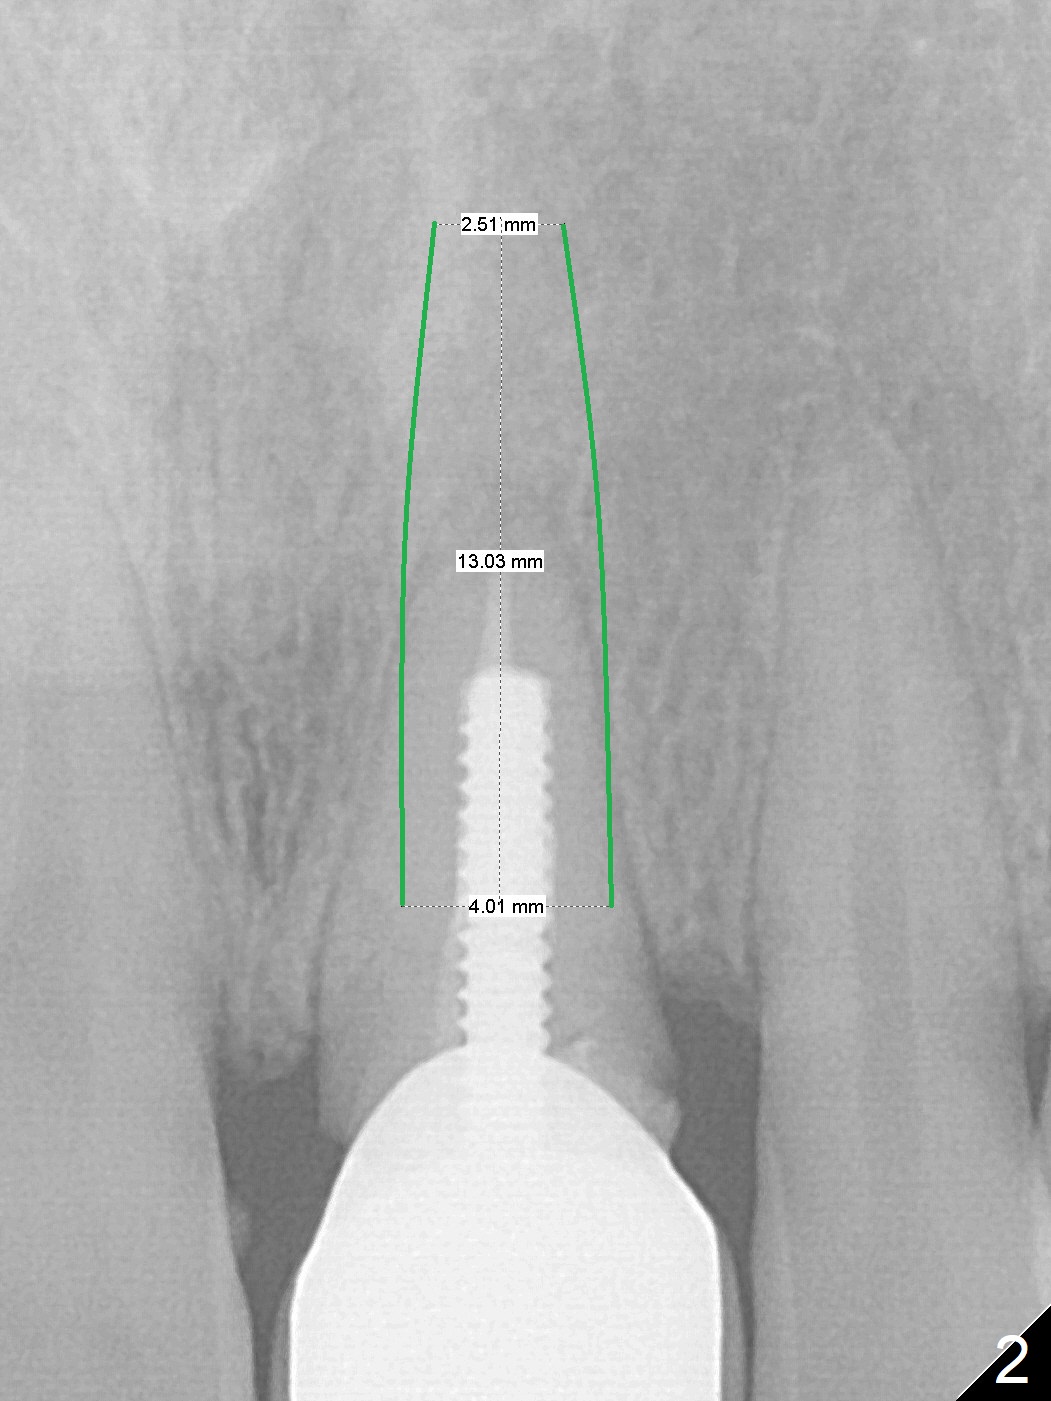

A 35-year-old woman's #9 fractures (Fig.1) because of blow by her child's head. Since a non-gold coated abutment will be used, an implant should be placed as palatal as possible (Fig.2). If the trajectory of the osteotomy turns out to be unacceptable, switch the other implant system with gold coated abutment. Perform socket shield, if extraction is difficult.